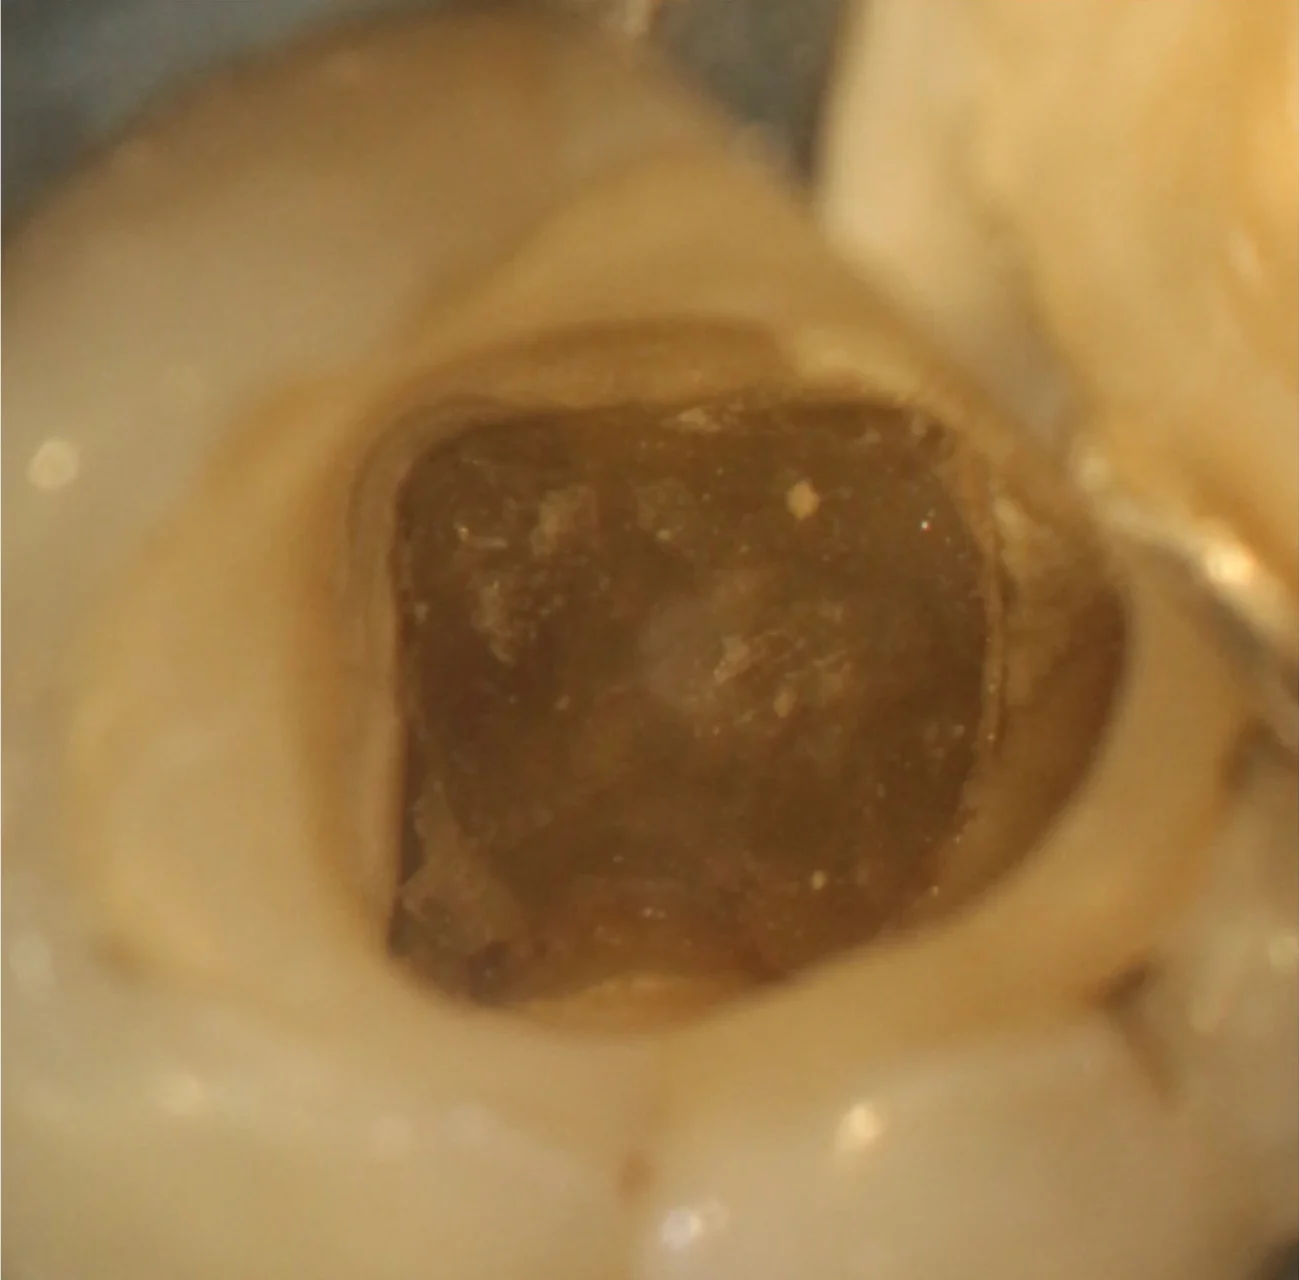

Localização de Canais Calcificados

Microscópio auxiliando na limpeza e localização de canais calcificados

Calcificação Pulpar

Após remoção do cálculo e localização dos canais

Auxílio do microscópio na localização e limpeza